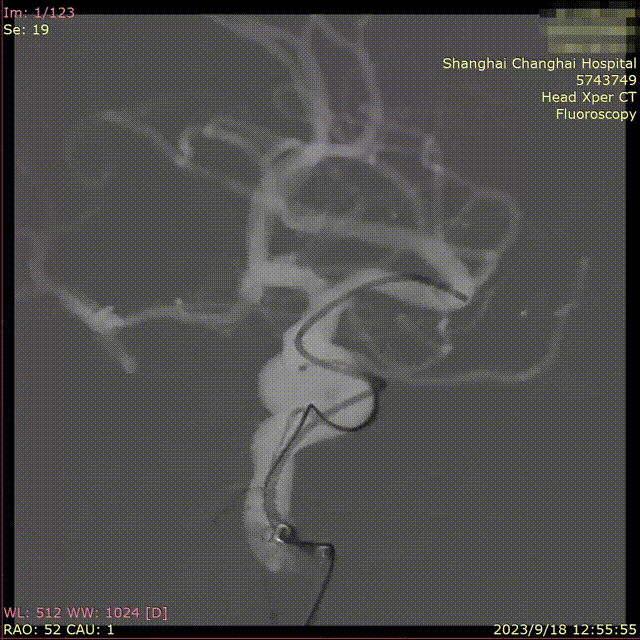

通过支架微导管,半释放支架(Lvis 5.5/30规格215530-CAS),首圈填入Nufairy™3D0730,箭头所指处为头端显影点,首圈在瘤内满意成篮。

图片